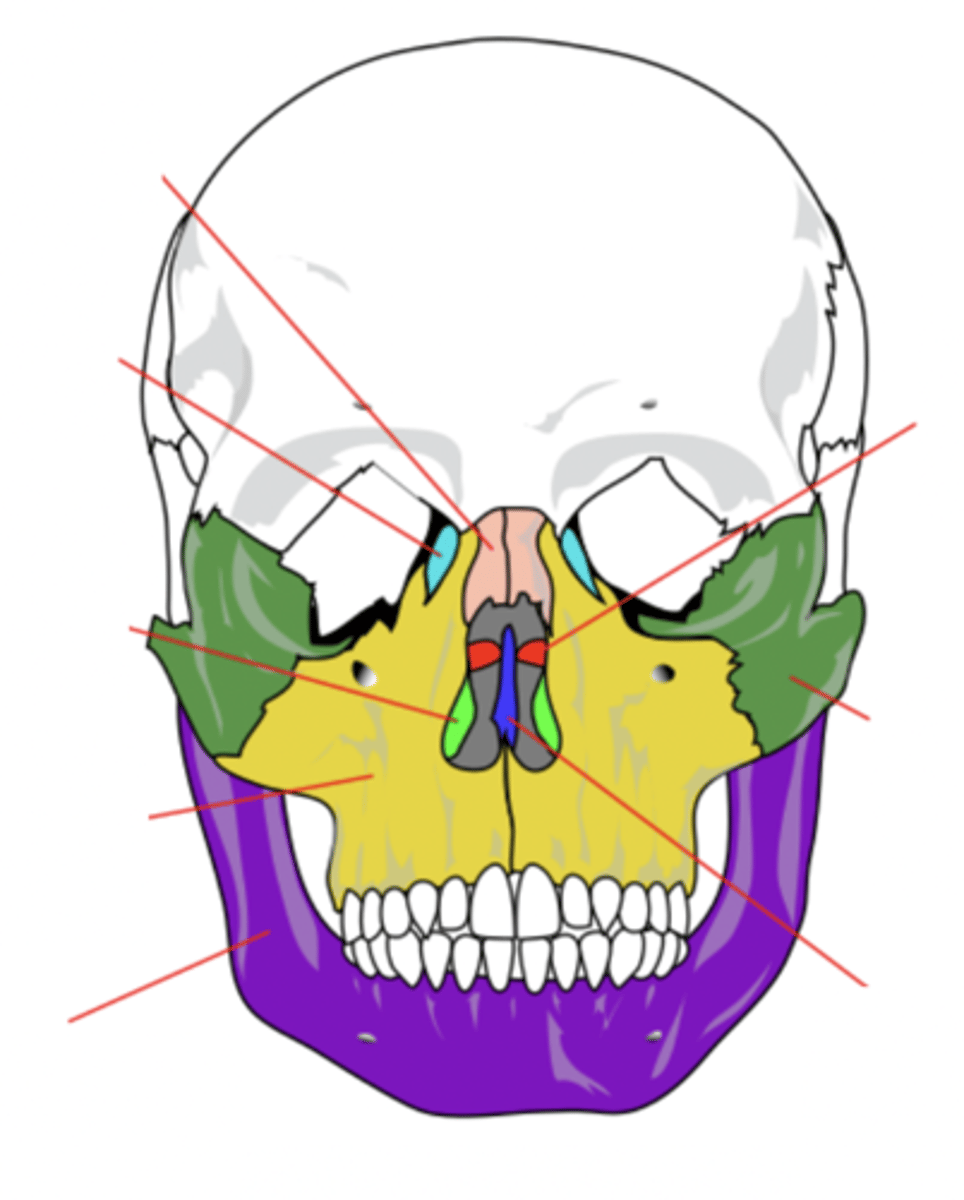

Facial Bones (14)

- Maxilla (2)

- Mandible

- Lacrimal (2)

- Palatine (2)

- Inferior conchae (2)

- Vomer

- Nasal (2)

- Zygomatic (2)

(Many Mammals Like Playing In Very Nice Zoos)

Maxilla Bone (2)

Upper jaw bone (yellow)

Mandible Bone

Lower jaw bone (purple)

Lacrimal Bone (2)

Small fragile bone making up part of the front inner walls of each eye socket and providing room for the passage of the lacrimal ducts (light blue)

Palatine Bone (2)

Bone that forms the hard palate and parts of the nose and orbits (red)

Inferior Conchae Bone (2)

The thin, scroll-like bones that form part of the interior of the nose (light green)

Vomer Bone

Bone that forms the inferior portion of the nasal septum (blue)

Nasal Bone (2)

Bone that forms the bridge of the nose (pink)

Zygomatic Bone (2)

Cheek bone (green)